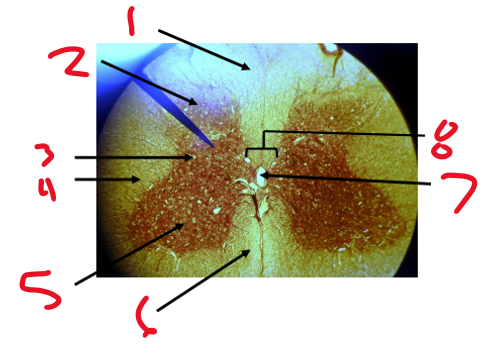

Name structure 1

Dorsal median sulcus

Name structure 2

Gray commissure

Name structure 3

Central canal

Name structure 4

Ventral median fissure

Dorsal funiculus

Dorsal horn

Lateral horn

Lateral funiculus

Name structure 5

Ventral horn

Name structure 6

Ventral funiculus

Name structure 7

Name structure 8